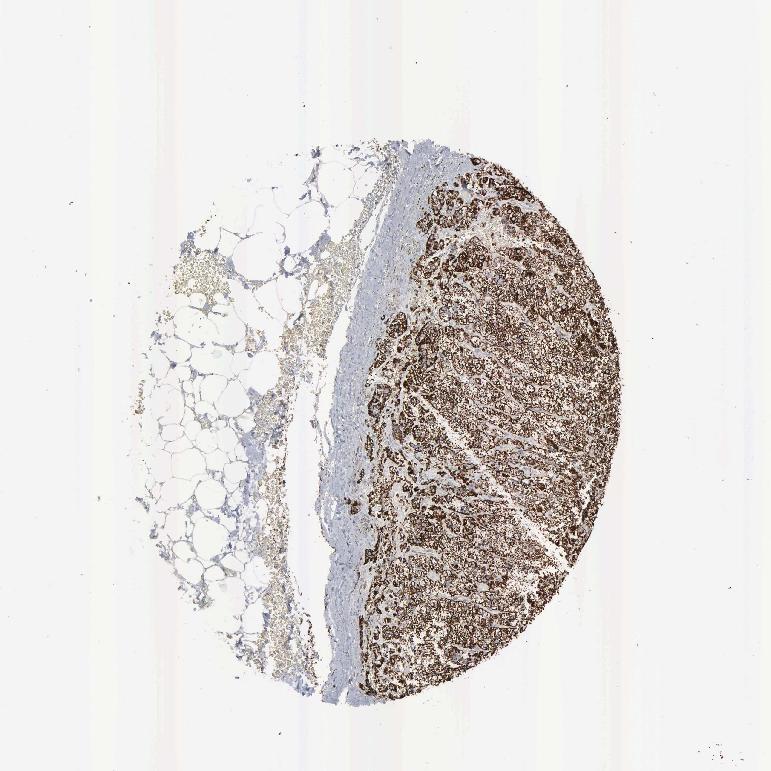

ADRENAL GLAND - Antibody stainingi

Antibody staining in the annotated cell types in the current human tissue is reported as not detected, low, medium, or high, based on conventional immunohistochemistry profiling in selected tissues. This score is based on the combination of the staining intensity and fraction of stained cells.

Each image is clickable and will lead to virtual microscopy that enables deeper exploration of all samples and also displays staining intensity scores, fraction scores and subcellular localization as well as patient and tissue information for each sample.

Antibody HPA000898Antibody CAB005219

Glandular cells HighHigh